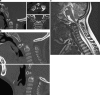

Background: The embryology of the bony craniovertebral junction (CVJ) is reviewed with the purpose of explaining the genesis and unusual configurations of the numerous congenital malformations in this region. Functionally, the bony CVJ can be divided into a central pillar consisting of the basiocciput and dental pivot and a two-tiered ring revolving round the central pivot, comprising the foramen magnum rim and occipital condyles above and the atlantal ring below. Embryologically, the central pillar and the surrounding rings descend from different primordia, and accordingly, developmental anomalies at the CVJ can also be segregated into those affecting the central pillar and those affecting the surrounding rings, respectively.

Discussion: A logical classification of this seemingly unwieldy group of malformations is thus possible based on their ontogenetic lineage, morbid anatomy, and clinical relevance. Representative examples of the main constituents of this classification scheme are given, and their surgical treatments are selectively discussed.